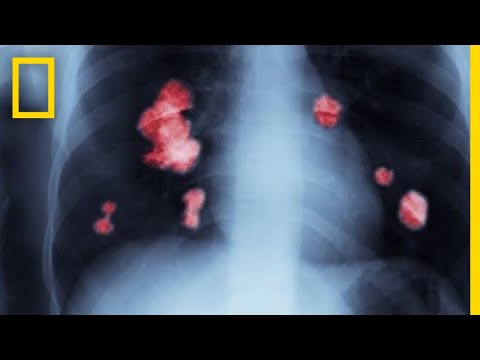

Рак лёгких — самый смертоносный из видов рака. Скрининг может спасти тысячи жизней, так почему же он не стал нормой? Нажмите здесь, чтобы подписаться на канал The Economist на YouTube: Рак лёгких уносит больше жизней, чем любая другая форма опухоли. Примерно девять из десяти человек умирают в течение пяти лет после постановки диагноза. При раннем выявлении рака большинство пациентов можно вылечить. Однако врачам сложно поставить ранний диагноз, поскольку симптомы проявляются только на поздних стадиях, когда рак распространился на другие органы. Некоторые эксперты считают, что врачам следует проводить скрининг людей из группы высокого риска, чтобы обнаружить рак лёгких до появления симптомов. В рамках национального исследования скрининга лёгких в Америке 53 000 нынешних и бывших заядлых курильщиков ежегодно в течение трёх лет проходили рентгенографию или компьютерную томографию. Результаты, опубликованные в 2011 году, показали, что скрининг с помощью КТ действительно спасал жизни. Но возникла проблема. Слишком много узлов, обнаруженных во время скрининга, не были раковыми. Это называется ложноположительным результатом. Ложноположительные результаты могут навредить пациентам, проходящим опасные последующие процедуры, такие как биопсия, даже если у них нет рака. Это также может повлиять на их психическое здоровье, а ложноположительные результаты увеличивают расходы на здравоохранение. Согласно новым данным Всемирной организации здравоохранения, этот вред можно значительно снизить, следуя другому протоколу. Вместо того, чтобы считать все уплотнения положительным результатом, врачам теперь рекомендуется игнорировать даже самые маленькие узелки и считать их отрицательным результатом. Это позволило вдвое снизить частоту ложноположительных результатов. Из каждых 1000 человек, прошедших сканирование, 356 человек нуждались в повторном тестировании по старому протоколу. С новым протоколом это число сократилось до 180. Осложнения при повторном тестировании также снизились. Эти результаты обнадеживают. Многие страны ждут полного отчета по другому исследованию под названием Nelson, прежде чем принять решение о создании полноценных программ скрининга. Предварительные данные исследования Нельсона свидетельствуют о том, что скрининг снижает смертность от рака легких среди мужчин из группы высокого риска на 26% и на 61% среди женщин. Если удастся найти баланс между стоимостью и преимуществами скрининга, рак легких больше не будет смертным приговором. Подробнее о фильмах Economist Films: Посмотрите полный видеокаталог The Economist: Подпишитесь на The Economist в Facebook: / theeconomist Подпишитесь на The Economist в Twitter: / theeconomist Подпишитесь на нас в Instagram: / theeconomist Подпишитесь на нас в Medium: / the_economist